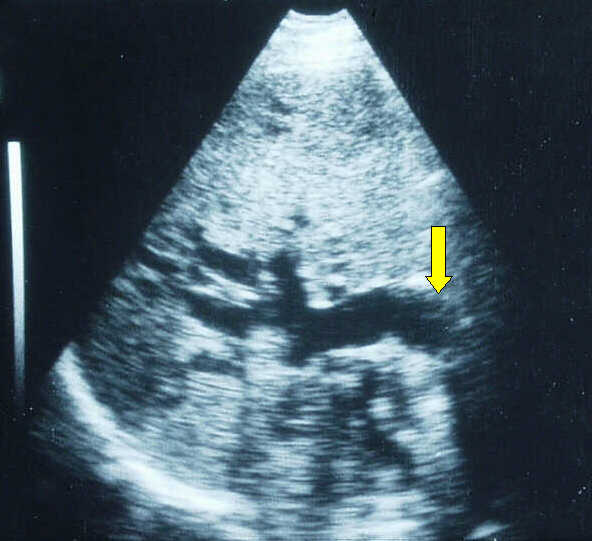

Right

intercostal scan in a patient with pancreatic head cancer not demonstrated by

ultrasound. The marked dilatation of the common bile duct (yellow arrow) and of

the intrahepatic biliary tree is well shown.